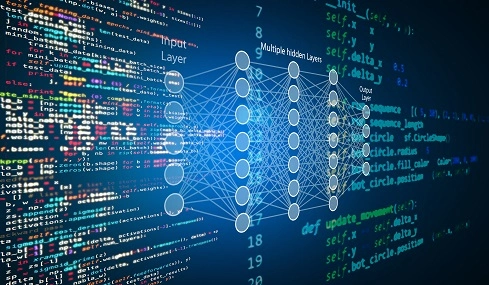

I'm 4th year at Northeastern University majoring in Data Science and Behavioral Neuroscience. I'm incredibly interested in the intersection of technology and healthcare, especially in how we can apply advanced data science techniques to understand and treat neurodegeneration.